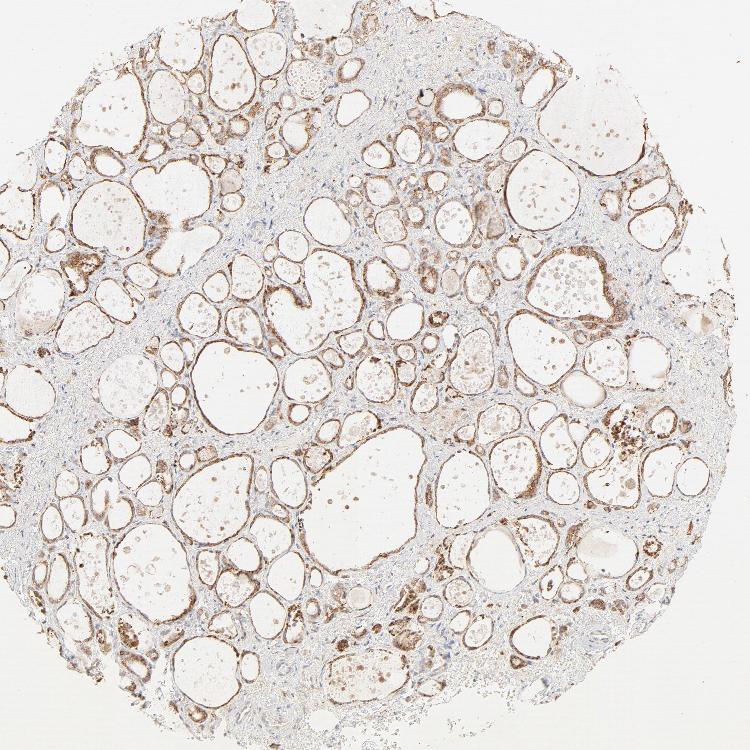

THYROID GLAND - Antibody stainingi

Antibody staining in the annotated cell types in the current human tissue is reported as not detected, low, medium, or high, based on conventional immunohistochemistry profiling in selected tissues. This score is based on the combination of the staining intensity and fraction of stained cells.

Each image is clickable and will lead to virtual microscopy that enables deeper exploration of all samples and also displays staining intensity scores, fraction scores and subcellular localization as well as patient and tissue information for each sample.

Antibody HPA003584

Glandular cells High